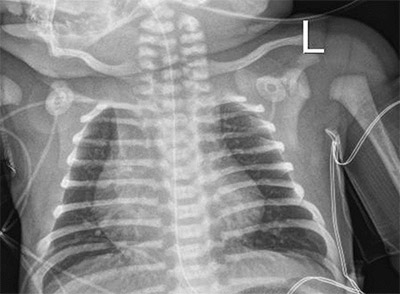

A full-term newborn with respiratory distress and right upper lobe atelectasis should raise suspicion for primary ciliary dyskinesia. This may be associated with congenital heart disease (as in this case with cardiomegaly, also noted on the chest X-ray). (Source: Image courtesy of Aliva De, MD.)